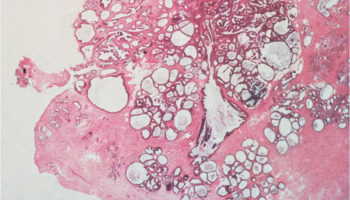

A rare type of fibroepithelial lesion of the breast that contains neoplastic stromal cells and associated benign epithelium. Phyllodes tumors differ from fibroadenomas because they are more cellular and have a unique “leaf-like” pattern of growth. Phyllodes tumors can be benign, borderline (i.e., in between benign and malignant), or malignant and all require surgical excision.